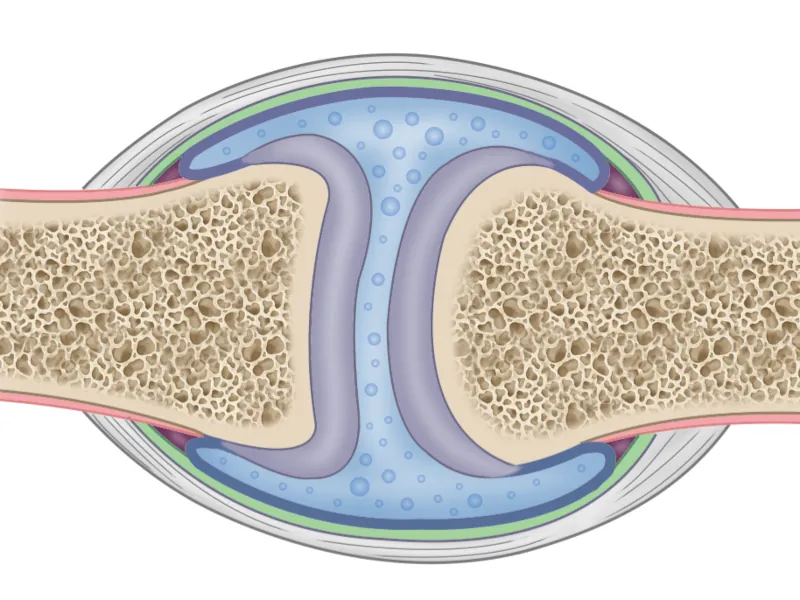

Most of the joints in the body provide a wide range of motion because they have space between adjacent bones that are filled with lubricating fluid. These are the joints of the knees, shoulders, hips, elbows, wrists, fingers, and upper neck, where flexibility is critical. The bones in such a non-rigid connection are supported by ligaments and tendons on the outside of the joint.

In fact, each vertebra is connected to the neighboring one by three joints: the main structure, called the vertebral disc, consists of cartilaginous tissue and plays the role of a shock absorber, and the other two, called facet joints, are filled with lubricant and work as hinges. This intricate design keeps the vertebral column stable and strong while allowing it to twist, or bend to the front, back, or side.

1. Air bubbles form and collapse

If a client’s joints make noise during a massage, it is most often a faint sizzling sound, similar to the sound of opening a soda can. As is known, soda water fizzes out and bubbles after opening because of the carbon dioxide gas that is dissolved in the liquid under pressure. With a sharp decrease in pressure, the liquefied gas is re-vaporized forming bursting bubbles.

Likewise, nitrogen gas is dissolved under pressure in the joint cavity fluid. If the cavity expands sharply, the pressure therein quickly drops, and the gas is also released in the form of bubbles. When the joint is stretched far enough, the pressure in the cavity falls so low that these bubbles burst, producing a sizzling sound. After some time, the bones, tendons, and ligaments return to their natural position, restoring the previous pressure in the cavity – so that in about 20-30 minutes nitrogen gas is completely dissolved in the joint fluid again.

This can happen to any movable joint in the body, but the intensity of the “boiling” process depends on the capability of the joint to stretch rapidly beyond its normal limits. The joints of fingers are the easiest ones to crack, and we’ve probably all cracked our knuckles at one time or another.

Cavitation itself does not bring any harm or benefit. The sizzling sound when manipulating joints does not indicate anything to the massage therapist, except that these joints have good elasticity.